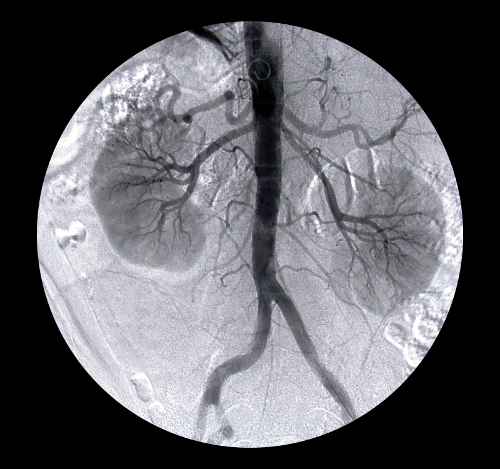

Almeno un quarto dei potenziali donatori presentavano anomalie tra le quali la più comune era la presenza di calcoli renali, presenti nel 210% circa dei partecipanti.

Le anomalie, tra le quali il restringimento delle arterie renali, la presenza di cicatrici e di accumuli di tessuto nel rene (alcuni dei quali segnali di formazioni tumorali) erano comuni nei pazienti di età superiore ai 50 anni.

Secondo i ricercatori se i risultati evidenziano il miglioramento delle tecnologie di imaging, che permettono di scoprire anche le più sottili e minime anomalie nei reni, ancora non è chiaro se queste possono essere benigne o dannose per l’organismo sulla lunga durata.